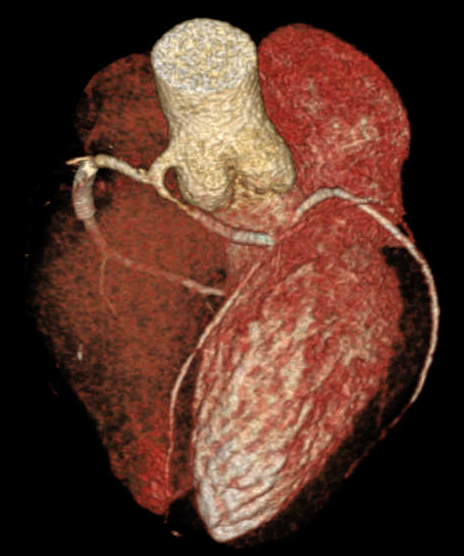

Percutaneous Coronary Intervention (PCI) of mid RCA: Common coronary trunk ostium was engaged with a 6F JR4.0 guiding catheter with meticulous care to prevent any ostial injury. Mid RCA lesion crossed with a 0.014¡± BMW wire. Predilated the lesion with 2.5x12mm semi compliant balloon. Stenting of the lesion was done using a DES (3.5x23mm) with final good result. A cardiac CT was done following PCI which confirmed the angiographic findings and found normal subpulmonic non-malignant course of left branch vessel (Lipton's class R II A).

Anomalous origin of left coronary artery from right aortic sinus as a common trunk is very rare. Percutaneous coronary intervention in such anomalies is scarcely reported. We are presenting such a very rare case of percutaneous coronary intervention in a single coronary artery arising from RCC with non-malignant course (Lipton's class R II A). Cannulation and PCI in such anomalous vessel are challenging and increase the technical complexity of the procedure. Meticulous care is needed to avoid injury to the common origin while cannulating as it can lead to catastrophe. Fortunately, in our case, we could cannulate the vessel with JR guiding catheter and complete the procedure successfully.